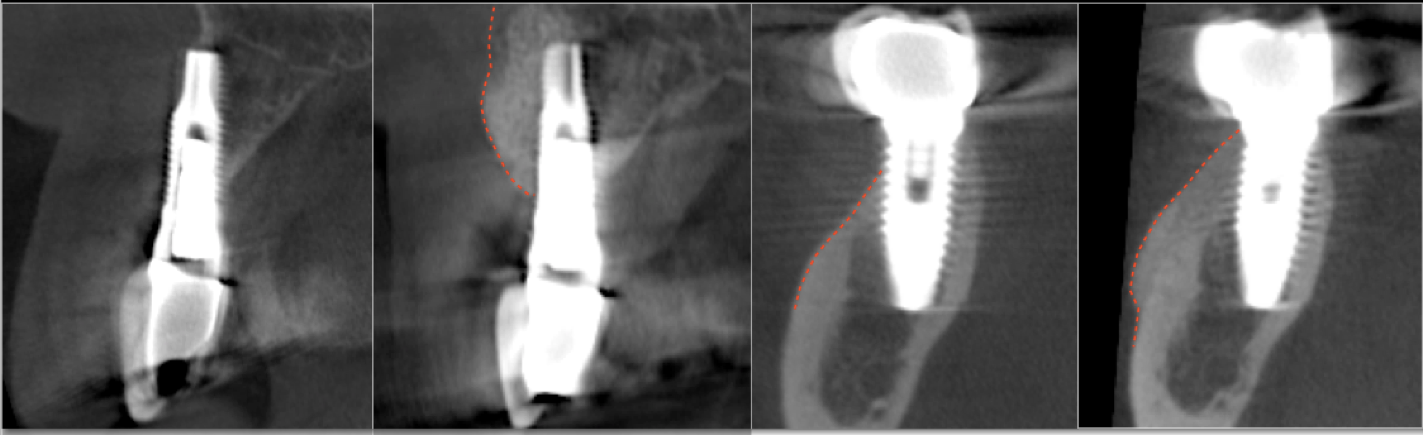

Bone regeneration over exposed implant surfaces is a novel application of the S.M.A.R.T. technique. Bone may be absent for a variety of reasons, usually related to placement or bone remodeling.

As bone loss advances, implants may need to be removed and treatment started all over again. Traditional techniques have shown limited success in regenerating bone over implants. The S.M.A.R.T. technique has been successful in treating exposed implant surfaces with up to 3 year follow up. It provides a simplified, predictable and cost-effective alternative, with less patient discomfort.